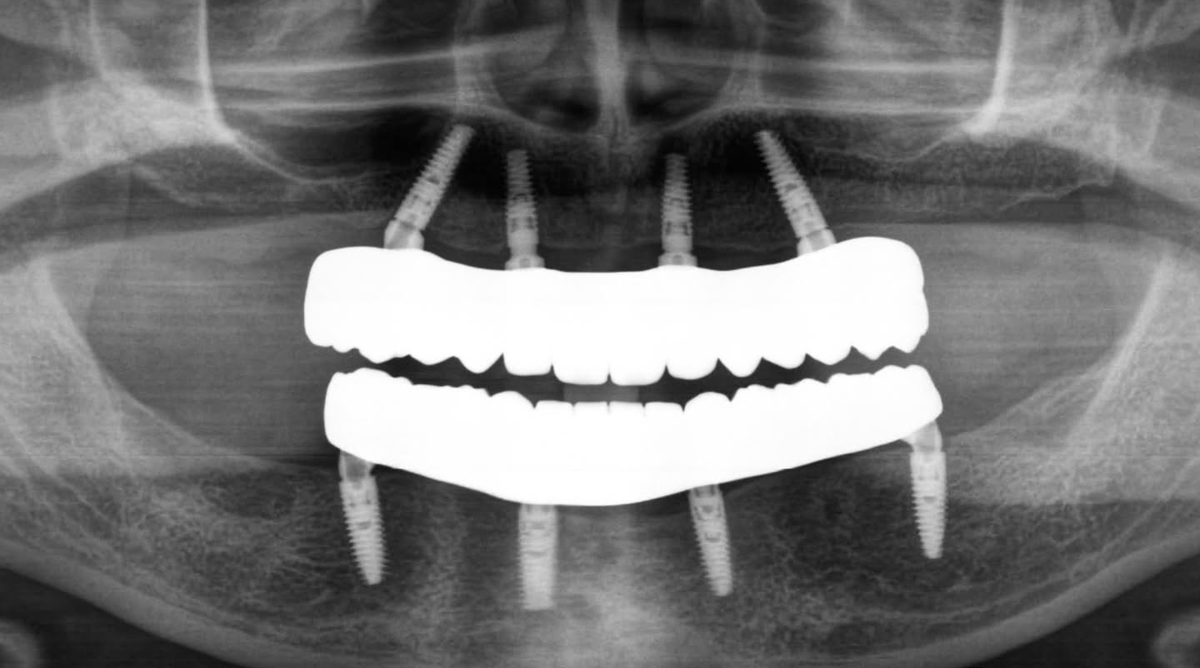

За этими словами — сложная, но чётко спланированная реабилитация по протоколу "всё-на-четырёх»:

✔ планирование в @3shape,

✔ установка 4 имплантов на нижнюю челюсть и верхнюю челюсть (MIS C1) + костная пластика с использованием биоматериалов B2S,

✔ установка multi-unit абатментов,

✔ временное протезирование в день операции,

✔ через 6 месяцев установка постоянных несъёмных протезов на обеих челюстях.

До и после.